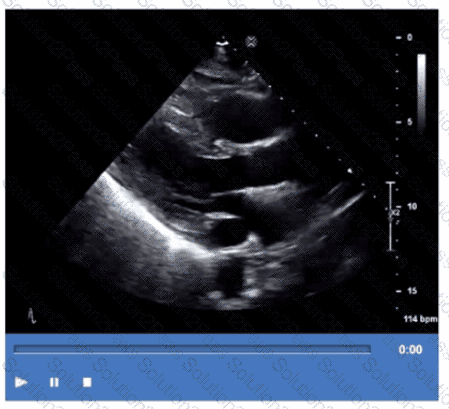

Which finding is demonstrated in this video?